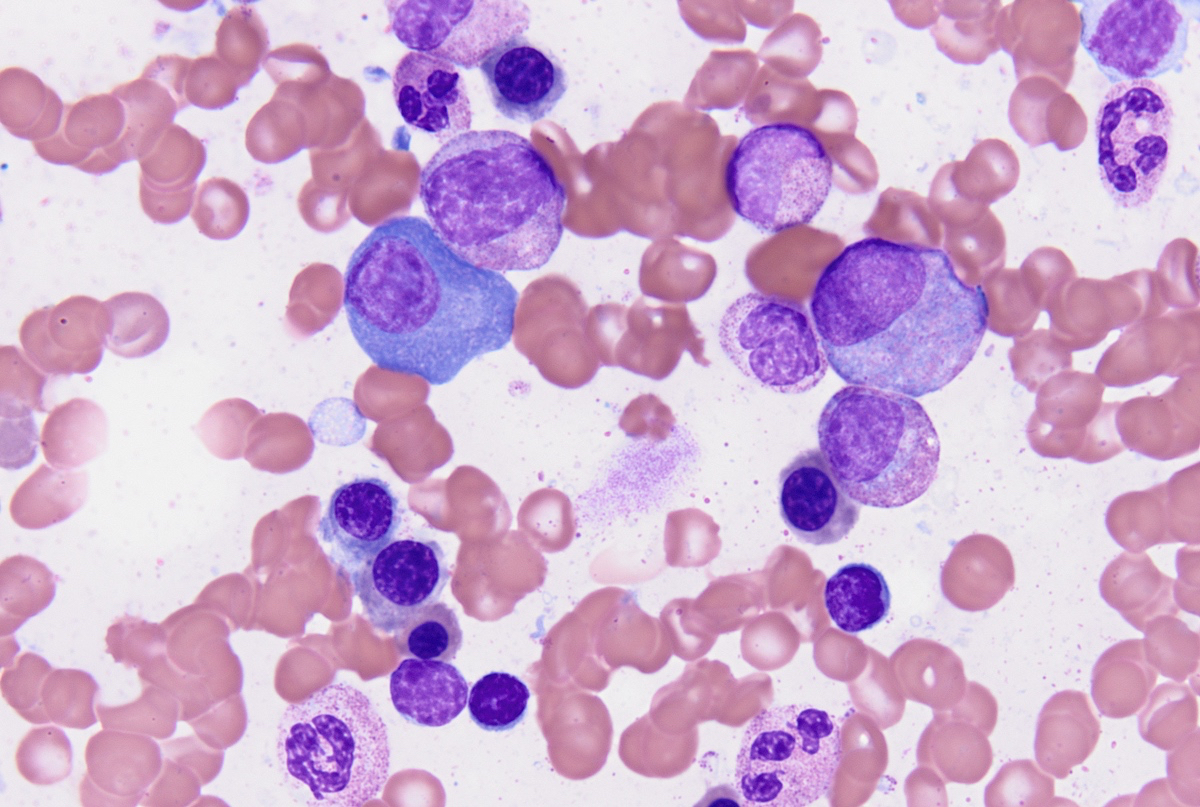

Cytology description

- Cytology can assess plasma cell morphology (e.g., mature, immature, plasmablastic) but number of plasma cells present may vary substantially from the core biopsy

- Mature plasma cells: oval with abundant basophilic cytoplasm, perinuclear hof, round eccentric nuclei, clock face chromatin and indiscernible nucleoli

- Immature plasma cells: higher nuclear to cytoplasmic ratio, more abundant cytoplasm and hof region compared to plasmablastic, more dispersed chromatin, often prominent nucleoli

- Plasmablastic: less abundant cytoplasm with little or no hof region, fine reticular chromatin, large nucleus (> 10 microns) or large nucleolus (> 2 microns) (Blood 1998;91:2501)

- Pleomorphic: multinucleated, polylobated

- Rare cases may have small, lymphoid appearing plasma cells or plasma cells with marked nuclear lobation

- Immature or pleomorphic features are rare in reactive plasma cell proliferations

- Morphologic features:

- Mott cells / morula cells: multiple grape-like cytoplasmic inclusions comprised of crystalized immunoglobulin

- Russell bodies: hyaline intracytoplasmic inclusions

- Flame cells: vermillion staining glycogen rich IgA in cytoplasmic projections (American Society of Hematology: Flame Cells in Multiple Myeloma [Accessed 26 May 2022])

- Pseudo-Gaucher cells / thesaurocytes: overstuffed fibrils (J Clin Pathol 1976;29:916)

- Cytoplasmic crystals: occasional in myeloma, common in adult Fanconi syndrome (Am J Clin Pathol 1983;80:224)

- Dutcher body: pale staining immunoglobulin filled cytoplasm invaginating into the nucleus and appearing as an intranuclear inclusion, single and usually large, more common in IgA myeloma

Peripheral smear description

- Rouleaux formation: erythrocytes resemble stacked coins; related to quantity and type of M protein, not specific and may be caused by alterations in other plasma proteins (Biophys J 2000;78:2470, American Society of Hematology: Rouleaux Formation [Accessed 26 May 2022])

- Leukoerythroblastic reaction can occur with extensive marrow involvement

- Circulating plasma cells can be seen in ~15% of cases, usually small numbers not meeting criteria for plasma cell leukemia (> 2 x 109/L or 20% of the leukocyte count)